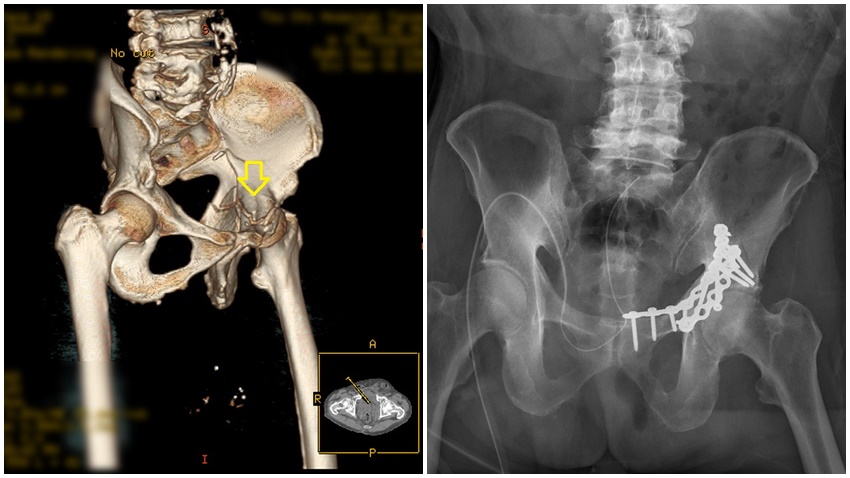

股骨轉子間骨折一般以骨折復位內固定治療為主。傳統手術治療,以鋼板鋼釘固定骨折,傷口大,流血多,復原期長,固定沒有這麼穩定,「微創閉鎖復位鋼釘固定」手術傷口小,流血比較少,復原力比較快。這位奶奶微創傷口分別為4公分、2公分和1公分,手術約40分鐘即復位完成,3天就順利出院。

▲由圖中可明顯看出骨折處與手術修復狀況。